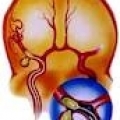

Артериовенозная фистула — патологическое сообщение между артерией и веной, по которому движется кровь, минуя капиллярную сеть. В норме артериовенозных фистул не существует. Существует несколько причин развития артериовенозных фистул.

Они могут  быть как врожденными ( связаны с мутациями в генах, отвечающих за нормальный рост сосудов), так и приобретенными – следствие различных травм (тупых травм, при пулевых или ножевых ранениях, операциях). Иногда фистулы специально создаются у больных, которым необходим гемодиализ. Как при патологических, так и при медицинских фистулах формируется прямое соединение между артериями и венами в обход мельчайших сосудов.